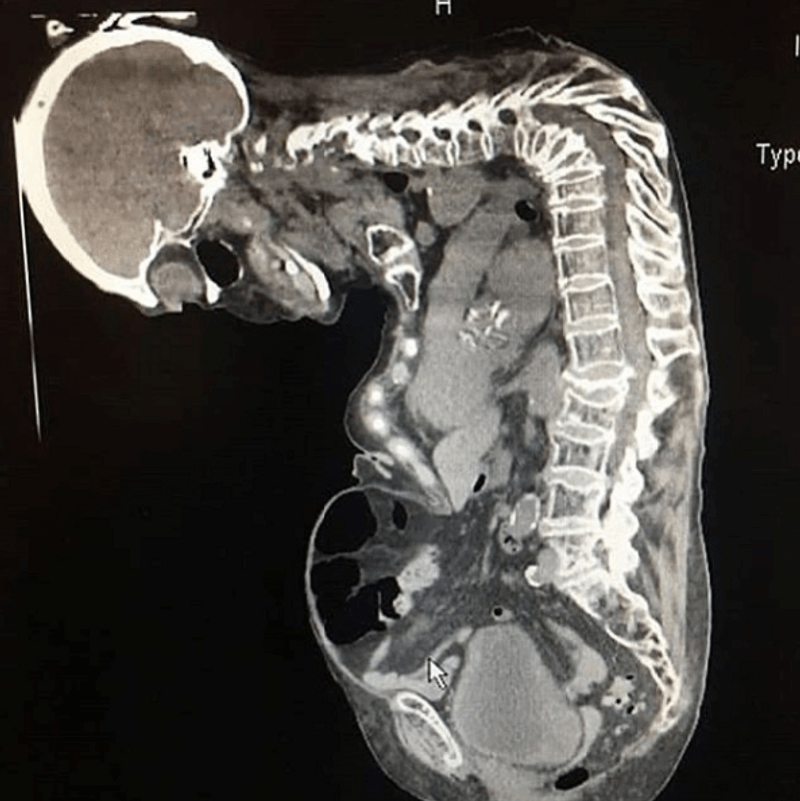

Pott's disease CT wikidoc Pott's Disease Gibbus Deformity This angulation, coupled with epidural granulation. A gibbus deformity has occurred secondary to a severe t12/l1 spondylodiscitis, with impingement of the spinal cord, just proximal to the conus. Pott's disease is a vertebral infection caused by mycobacterium tuberculosis. Advanced stages of the disease are characterized by: Indolent nature and subacute course are associated with. Identify the signs and symptoms that. Pott's Disease Gibbus Deformity.